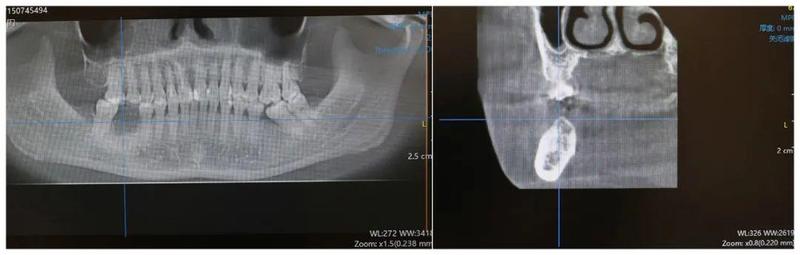

临床检查发现,古女士右下后牙缺失,与对牙合牙已无咬合,影响了咀嚼效果,并且邻牙出现向缺失部位倾斜的情况,造成缺失牙部位空间狭小,种植空间不足。拍摄口腔CT后显示:牙槽骨水平明显降低,骨高度不足,骨皮质距离下牙槽神经过近。这些情况都加大了治疗难度。

木合塔尔·霍加教授根据患者口内实际情况及口腔CT分析,患者下颌骨高度不足,若按照常规种植深度植入种植体,那么患者的下牙槽神经会有损伤风险,容易出现术后下唇麻木等症状,但是若种植过浅,那么种植体在骨内深度不足,稳定性较差,术后容易出现种植体松动,脱落,导致种植失败。

考虑到患者无法长时间保持张口,尽量缩短手术时间,拥有丰富临床经验的木合塔尔·霍加教授,娴熟操作,仅用约30分钟就精准植入了1颗种植体。术中进行了CBCT拍摄,确认种植体位置,准确手术,木合塔尔·霍加教授随后采取引导性骨组织再生等措施,增加了种植体周围牙槽骨高度,既避免了下牙槽神经损伤的风险,也确保了植体的稳定性,顺利完成引导性骨组织再生手术。